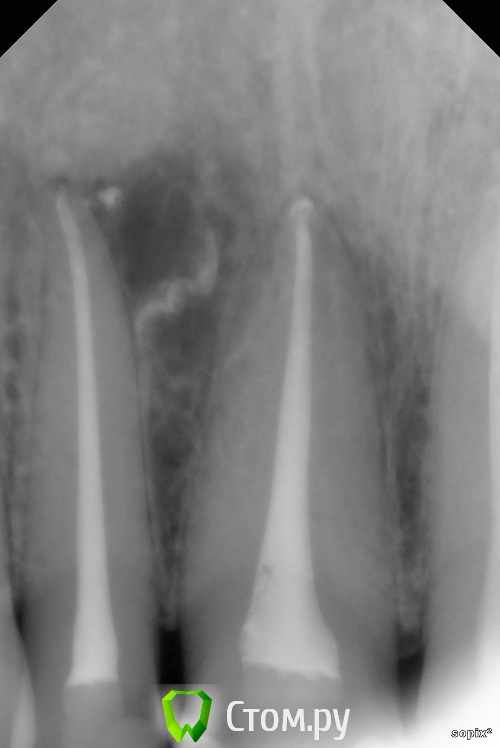

Dr.Sham Опубликовано 9 ноября, 2014 Поделиться Опубликовано 9 ноября, 2014 (изменено) Пришла пациентка за винирами, сделали снимки, увидили красоту Виниры на время отложили.Начал лечить, получил обострение, отмылся повторно, симптомы ушли.2 раза кальций поменял, т.к. после первого раза еще канал влажный был.Запаковал или волной, или сквирт был, уже не вспомнить.Вот результаты, критикуйте 05.1209.1311.14 Изменено 9 ноября, 2014 пользователем Dr.Sham 11 Ссылка на комментарий